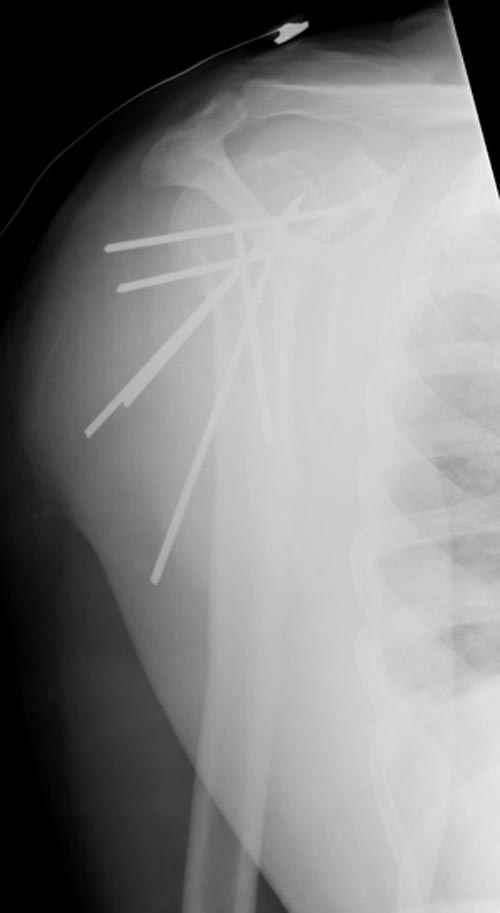

Здесь случай перелома-вывиха плеча, больному 56 лет, после "дважды" закрытой неудачной репозиции, опять же ургентно взяли в операционную, после полного общего обезболивания попытались сделать репозицию, и фиксацию провели спицами.

Больной находился в повязке, примерно напоминяющей косыночную, рекомендованы движения в локтевом суставе и маятниковые движения в плече, спицы удалены в три недели (были случаи миграции)

Сегодня взял больного повторно в операционную, не скажу, что повторная репозиция через неделю после первой попытки, была простая.

После удаления спиц попытался манипулировать отломками, но безуспешно, поэтому пришлось пользоваться периостальным элеватором, чтобы устранить смещение отломков и перепровести спицы. Проверил и перепроверил стабильность фиксации под ЭОПом, завтра Рг- будет готов, вот и поглядим....